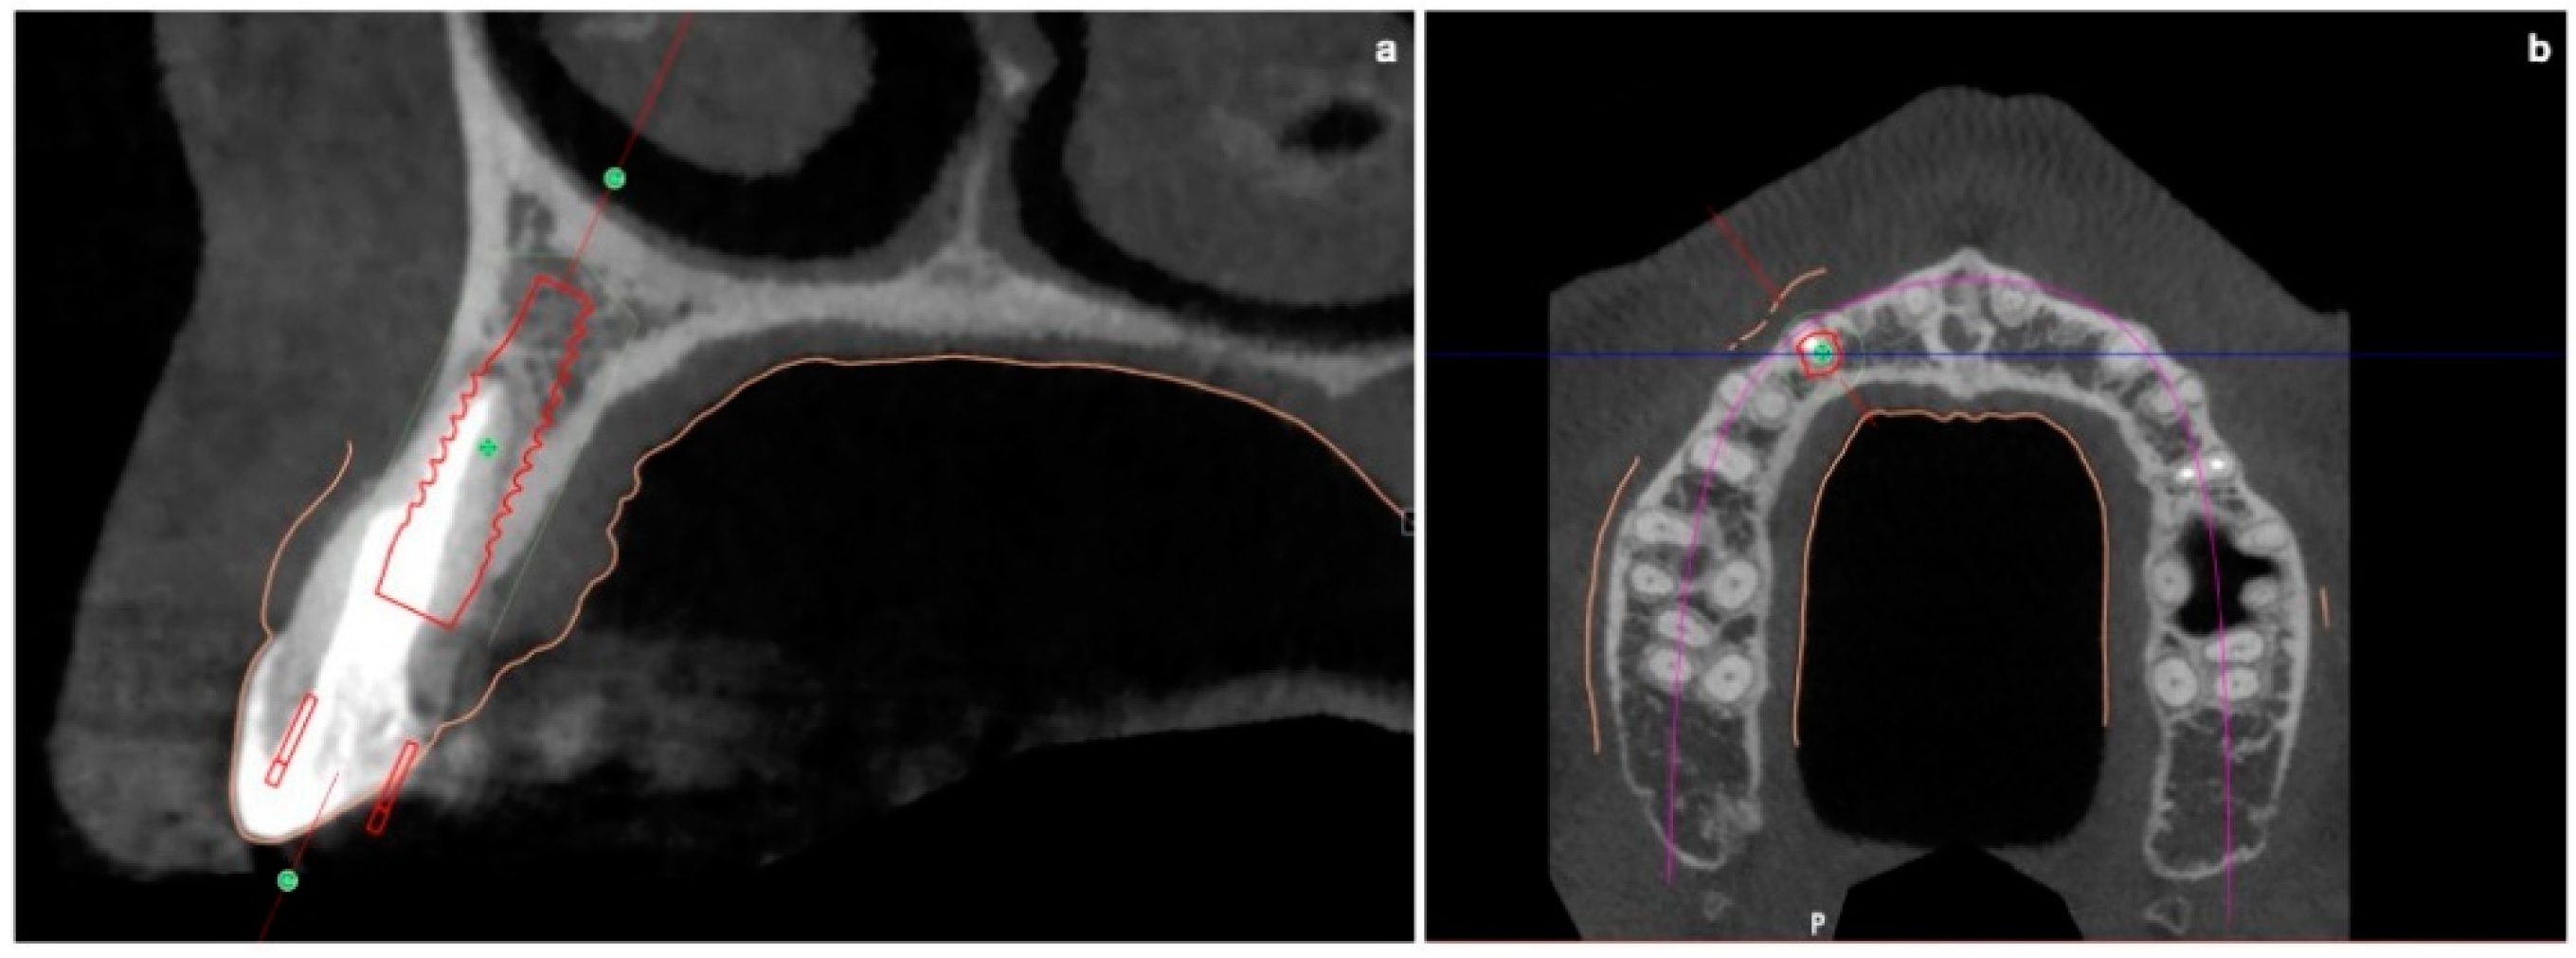

Prior to the surgery, CBCT was requested in order to plan a fully guided implant insertion.

The mean axis of the implant coincided with the most palatal extension of the cuspid of the canine of the predetermined final restoration. During planning, it was decided to use a Prama implant with a short neck of 1.8 mm, a diameter of 3.8 mm and a length of 11.5 mm.

The apical-coronal planning of implant placement was chosen in relation to the esthetically ideal position of the buccal soft-tissue margin of the final restoration; the smooth implant collar was 2 mm apical with respect to the ideal position of the buccal soft-tissue margin of the final restoration. In fact, in an apico-coronal direction, the endosseous implant portion is positioned 3.5–4 mm apical with respect to an imaginary horizontal line that is placed at the same level of the gingival margin of the natural homologous tooth, which always represents the reference point for implant positioning. The use of transmucosal implants (in which the height of the polished neck can be chosen in relation to the peri-implant transmucosal portion) is useful for displacing the implant–abutment connection away from the bone crest. This reduces bone resorption and makes hygiene maintenance easier both for the patient and the hygienist.

The buccal bone wall was extremely thin but partially maintained with 2 mm of buccal bone dehiscence (Figure 3a,b).

Figure 3. (a,b) Pre-surgical CBCT evaluation in order to perform guided implant insertion.